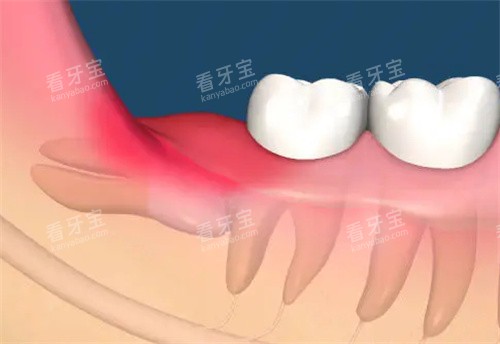

那是一个普通的周末早晨,我像往常一样刷牙时,突然感觉右后方的牙齿一阵刺痛。我赶紧对着镜子张大嘴,用手指轻轻触碰那个位置,果然摸到了一个明显的凹陷。我的心一下子沉了下去——我的智齿烂了个洞!

刚开始我还抱着侥幸心理,想着也许只是个小问题,用点降低炎症药就能好。但接下来的几天,疼痛越来越明显,尤其是吃东西的时候,那种钻心的痛让我不得不总是用左边咀嚼。晚上睡觉时,隐隐作痛的感觉更是让我辗转难眠。

实在受不了了,我终于鼓起勇气去了附近的牙科诊所。医生检查后告诉我:"这颗智齿已经蛀得很深了,而且位置很靠后,清洁起来特别困难。"